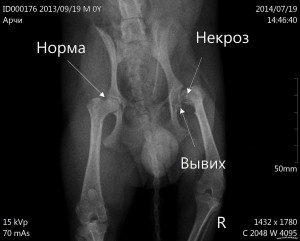

Необходимо отметить тот факт, что на ранних стадиях выявить асептический некроз при помощи рентгеновского обследования просто невозможно. На рентгеновских снимках можно увидеть заболевание только на второй, а то и третьей стадии. Если доктор отправляет пациента на рентген, то только теряет время.

Выявить диагноз на ранних стадиях можно только при помощи компьютерной или магнитно-резонансной томографии. Если же «стаж болезни» превысил год, а то и более, только тогда с помощью рентгеновского исследования можно выявить точный диагноз. Ультразвуковое исследование делать бесполезно для диагностики заболевания.